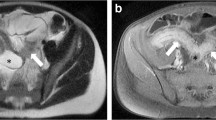

The IBD-RADS based on the above analysis are summarized in Fig. 3. In IBD-RADS, AE was the major criterion, and perianal fistula and VFP were auxiliary criteria. Limited small bowel disease, intestinal-fistula, and skip distribution were highly specific indicators, favoring the diagnosis of CD in particular. We proposed five grades according to the above indicators, and Fig. 3 shows the grade distribution in IBD patients, as detailed in Table 4. Grade 4 and 5 can be initially diagnosed as CD, with 94.3% (derivation) and 95.8% (validation) of CD patients being classified. Grade 3 met only the major criterion and was likely to be diagnosed with CD (57.1% (8/50) and. 50.0% (2/4)), with 2.2% (10/462) of CD patients classified into this category. Grade 1 and 2 did not meet the major criterion. Among them, Grade 1 did not have any imaging signs mentioned above, were less likely to be diagnosed with CD (3.6% (6/167) and 2.5% (1/40)) and preferred UC. Grade 2 met only the auxiliary criteria and also preferred UC. Figure 4 shows imaging and endoscopic images of three patients classified as Grade 5b (a-b) and Grade 1 (c), respectively.

Criterion, definitions, and interpretations of IBD-RADS, and its distribution in the two cohorts. IBD-RADS includes one major criterion, two auxiliary criteria, and three special support items. The grading system classifies patients into five grades, with Grade 4 and 5 further subdivided into three and two categories, respectively. Based on the distribution in the derivation and validation cohorts, we recommend that Grade 1 and 2 patients should be initially classified as UC, while Grade 3 and 4 are more indicative of CD. Patients classified as Grade 5 can be preliminarily classified as CD. CD, Crohn's disease; UC, Ulcerative colitis

CTE, pelvic MRI and endoscopic images of two Grade 5 CD patients and one Grade 1 grade UC patient. a The CTE images of a 24-year-old male with CD showed asymmetric enhancement (green arrow) and intestinal fistula (yellow asterisk). The visceral and subcutaneous fat were marker as yellow and blue, respectively, and the VSR is 1.19 (> 0.97, visceral fat predominance). He was classified as Grade 5b. b The CTE, pelvic MRI and endoscopic images of a 24-year-old male patient with CD showed discontinuous asymmetric enhancement (green arrow), perianal fistula (yellow arrow) and longitudinal ulcer (green asterisk), and the VSR was 2.55 (> 0.97, visceral fat predominance). He was classified as Grade 5b. c The CTE image of a 55-year-old female patient with UC showed symmetric enhancement of the sigmoid colon with a VSR of 0.38 (< 0.97). She was classified as Grade 1. CTE, CT enterography; CD, Crohn's disease; UC, Ulcerative colitis